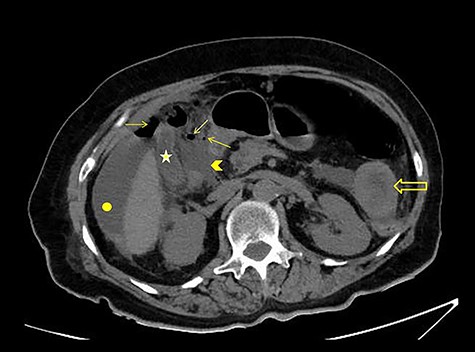

The patient was afebrile but hemodynamically unstable, with 115 bpm and a systolic pressure of 80 mmHg on presentation. Clinical examination revealed abdominal distension, diminished bowel sounds and severe tenderness with peritoneal signs in all of the abdominal quadrants. Her laboratory blood examination showed elevated number of neutrophils (7.77 K/μl), elevated C-reactive protein value (82.46 mg/dl) and decreased Na+ (119 mEq/l). After initial resuscitation, a computed tomography (CT) scan was performed. It showed free abdominal air and fluid in the peritoneal cavity, indicating an intestinal perforation (Figs 1–3).

CT scan with iv and without per os contrast media administration: communication of free air with stomach (line).